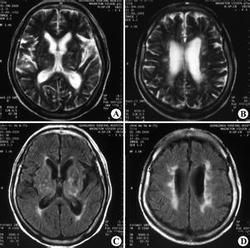

LA的MR表現

LA在MRI顯示兩側基本對稱的側腦室周圍腦白質T1WI為等、低信號,T2WI為高信號的片狀、點狀影,邊界模糊,常累及半卵圓中心、基底節區、放射冠等,液體恢復反轉序列(FLAIR)為高信號。由於FLAIR可顯示較多病灶,故懷疑LA的患者宜攝取FLAIR像。